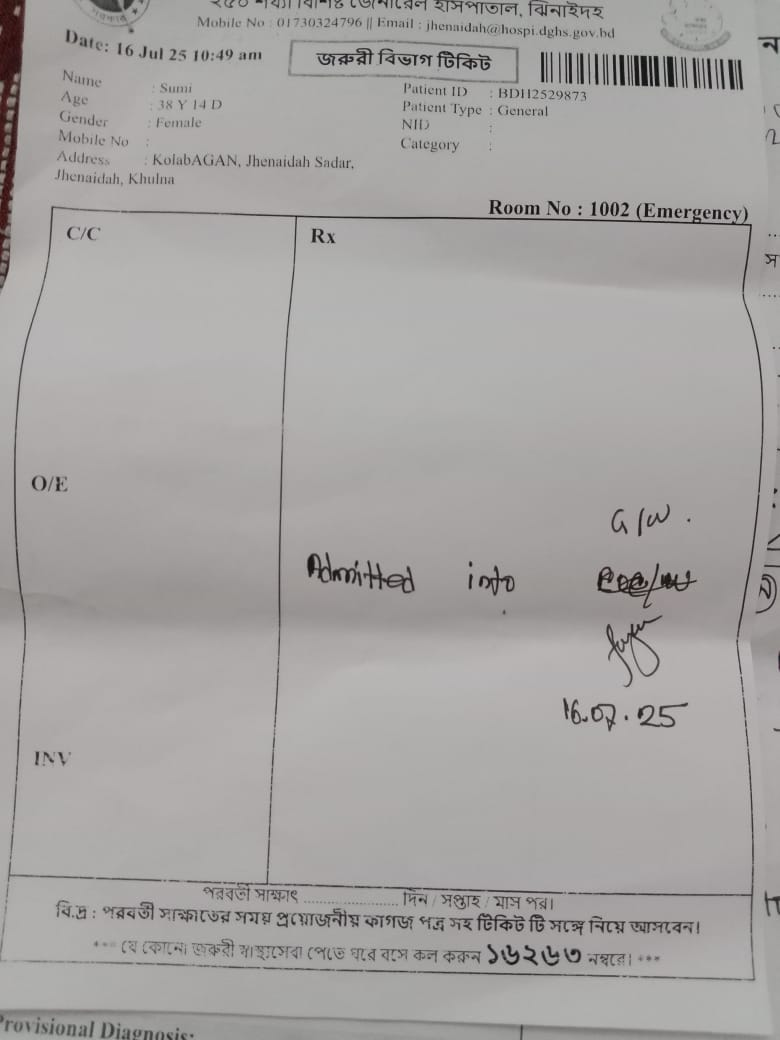

#250928D: তহুরা খাতুনের টিউমার অপারেশনের জন্য সাহায্যের হাত বাড়িয়েছেন; গ্রাম: কলাবাগান, জেলা: ঝিনাইদহ।